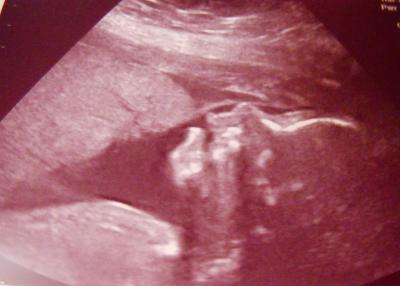

War supi toll. Es ist alles bestens. Unser kleiner Mann wiegt jetzt 580g und ist 28cm groß. Hier ist noch ein Bildchen. Da gibt er wohl gerade Küsschen.

Das ist ein tollen Profil und er hat den Mund offen. Er übt wohl schlucken Schön, dass auch bei dir alles gut ist und die Maße sind toll. LG Diana